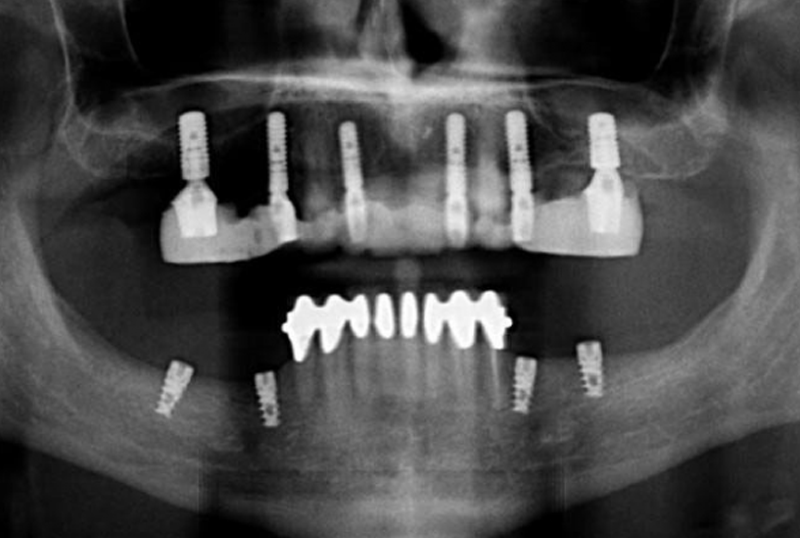

Implants are screw shaped that is placed in jawbone to replace a missing teeth. A crown is placed on this screw to look and function as the crown portion of the natural tooth. Dental implants are made majorly out of titanium material that suits the human body properly.